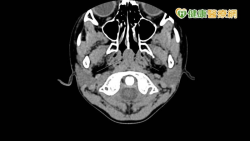

電腦斷層比天然輻射量高5倍 兒童照太多「罹癌機會增」 - 健康醫療網 - 健康養生新聞資訊網路媒體

2022-06-01 09:00:00 by 健康醫療網 @ 健康醫療網 [引用來源]

一名6歲男童,鼻咽部出現腫塊,被誤認為腫瘤,便替他安排頭、頸、胸、腹及骨盆等部位的電腦斷層(CT)檢查,結果在頭頸部發現是正常兒童會有的腺狀體淋巴組織,並非腫瘤,且其餘部位均無異常發現,然而電腦斷層掃描會讓兒童曝露於輻射的疑慮,中華民國放射線醫學會小兒影像診斷次專科委員會召集委員、臺大醫院核子醫學部主任彭信逢醫師表示,根據美國研究指出1,兒童接受電腦斷層檢查,每一次CT掃描,終身約增加...... [閱讀更多]